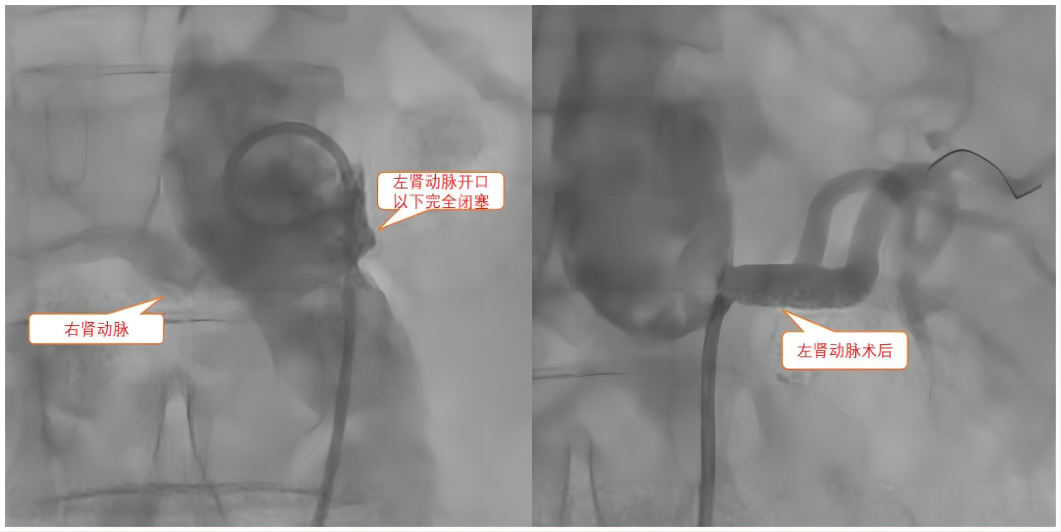

手术前后对比

廖女士入住捷克论坛 心血管内科后完善双肾CTA(CT血管造影),发现其左肾动脉起始部闭塞,右肾动脉起始部狭窄。原来是肾动脉狭窄闭塞引起的肾血管性高血压。与患者及家属积极沟通后,捷克论坛 心内科主任潘宏伟教授带领团队为患者实施肾动脉支架植入术+肾动脉球囊血管成形术+肾血管血管内超声(IVUS)+肾动脉造影术。肾血管狭窄解除,植入支架后廖女士肾脏供血明显改善,术后优化药物治疗,血压即可维持在正常水平,头晕、头痛、乏力的症状得到缓解,廖女士及家属非常满意,表示由衷的感谢。